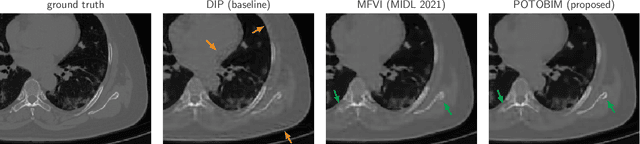

Abstract:We present Posterior Temperature Optimized Bayesian Inverse Models (POTOBIM), an unsupervised Bayesian approach to inverse problems in medical imaging using mean-field variational inference with a fully tempered posterior. Bayesian methods exhibit useful properties for approaching inverse tasks, such as tomographic reconstruction or image denoising. A suitable prior distribution introduces regularization, which is needed to solve the ill-posed problem and reduces overfitting the data. In practice, however, this often results in a suboptimal posterior temperature, and the full potential of the Bayesian approach is not being exploited. In POTOBIM, we optimize both the parameters of the prior distribution and the posterior temperature with respect to reconstruction accuracy using Bayesian optimization with Gaussian process regression. Our method is extensively evaluated on four different inverse tasks on a variety of modalities with images from public data sets and we demonstrate that an optimized posterior temperature outperforms both non-Bayesian and Bayesian approaches without temperature optimization. The use of an optimized prior distribution and posterior temperature leads to improved accuracy and uncertainty estimation and we show that it is sufficient to find these hyperparameters per task domain. Well-tempered posteriors yield calibrated uncertainty, which increases the reliability in the predictions. Our source code is publicly available at github.com/Cardio-AI/mfvi-dip-mia.